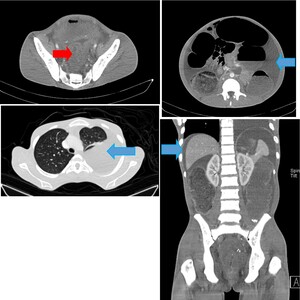

His complete blood count showed a hemoglobin of 9.4 g/dl (microcytic and hypochromic), leucocyte count of 9.22 × 109/l and a platelet count of 142×109/L. A plain chest x-ray revealed approximately 50% left pleural effusion (Figure 1), and abdominal-pelvic ultrasound concluded ascites, an ill-defined heterogenous pelvic mass with mild ascites. A contrasted CT-scan of the chest and abdomen showed symmetrical mural wall thickening measuring 4.2 cm of the sigmoid, upper, mid, and distal rectum measuring 16 cm in length, suggestive of a rectosigmoid tumor. The tumor was causing large bowel obstruction with ascites, and left sided pleural effusion (Figure 2).